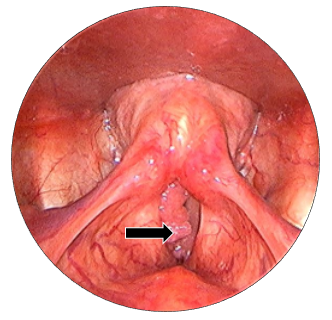

On examination he was sitting well with normal blood pressure. His SpO2 was 99% without any support. Oral cavity examination was normal. Rigid laryngocopy revealed a papillomatous pinkish swelling presented over anterior 2/3rd surface of right true vocal fold. This lesion reaches till anterior commissure and involving the anterior 1/3rd aspect of left true vocal fold.(Figure 1A-C) Both the true vocal folds were mobile with normal rest of the anatomical subsites. Patient underwent for computed tomography (CT) scan and it was reported as 8.3 x 8.8 x 7.1 mm nodular mildly enhancing soft tissue noted at anterior part of the right true vocal cord. (Figure 2) The patient was scheduled for microlaryngeal surgery under general anaesthesia.

Figure 1 (A to C) Laryngoscopic view of true vocal folds, showing papillomatous lesion over anterior 2/3rd true vocal fold, involving anterior commissure and left anterior1/3rd true vocal fold. bilateral true vocal folds were mobile.